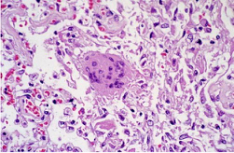

病理標本的一種,制作時將部分有病變的組織或臟器經過各種化學品和埋藏法的處理,使之固定硬化,在切片機上切成薄片,粘附在玻片上,染以各種顏色,供在顯微鏡下檢查,以觀察病理變化,作出病理診斷,為臨床診斷和治療提供幫助。病理切片病理切片的制作1.取材具體要求如下:(1)材料新鮮:取材組織愈新···